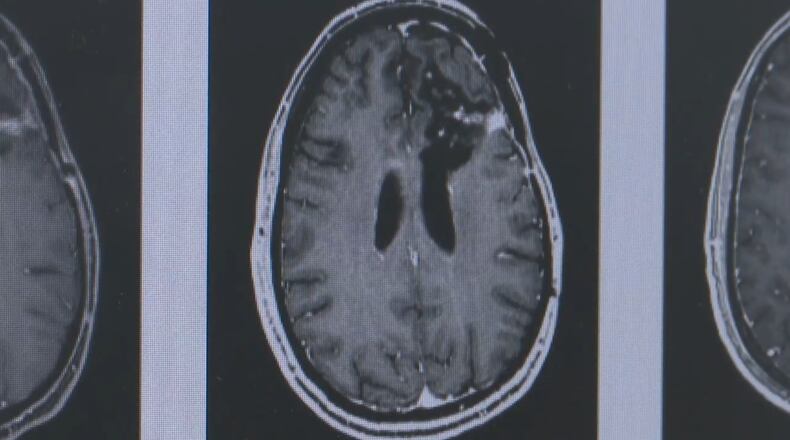

The personalized immunotherapy, UC said, works like a vaccine. The therapy is created from the patient’s own brain cancer cells and implanted into the patient’s stomach. It is then removed two days later, when the immune system has a chance to train itself to fight the tumor.

During the trial, patients will receive the new therapy after undergoing brain tumor neurosurgery. Once the therapy is removed, they’ll continue their standard care of outpatient chemotherapy and radiation.

“Survival with that standard of care with surgery, radiation and chemotherapy is about two years, and this therapy has the promise of extending survival beyond that,” Sengupta said.